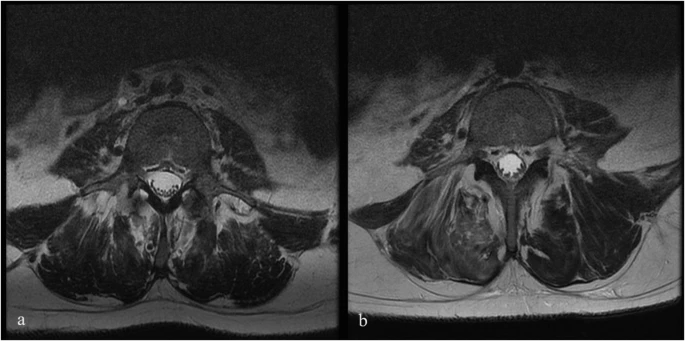

圖1:6號(hào)患者輸注前和輸注后MRI。

注射后血液和腦脊液檢查未發(fā)現(xiàn)異常。隨訪時(shí)MRI未見(jiàn)明顯變化;然而,在十名患者中,有八名檢測(cè)到馬尾神經(jīng)根的叢集輕度增加,有或沒(méi)有結(jié)節(jié)性增強(qiáng)的證據(jù)。在經(jīng)歷馬尾神經(jīng)根聚集或強(qiáng)化的患者中,沒(méi)有發(fā)現(xiàn)明顯的臨床相關(guān)性。圖1顯示了患者6的輸注前和隨訪MRI,該患者L4-S1水平的馬尾神經(jīng)根叢集輕度增加。表3突出顯示了所有患者干細(xì)胞注射前后的MRI變化。三名患者的SSEP有所改善。兩名患者與基線相比沒(méi)有任何變化,四名患者無(wú)法進(jìn)行解釋?zhuān)幻颊咴谡麄€(gè)研究期間具有正常的SSEP。表4突出顯示了SSEP 的發(fā)現(xiàn)和解釋。